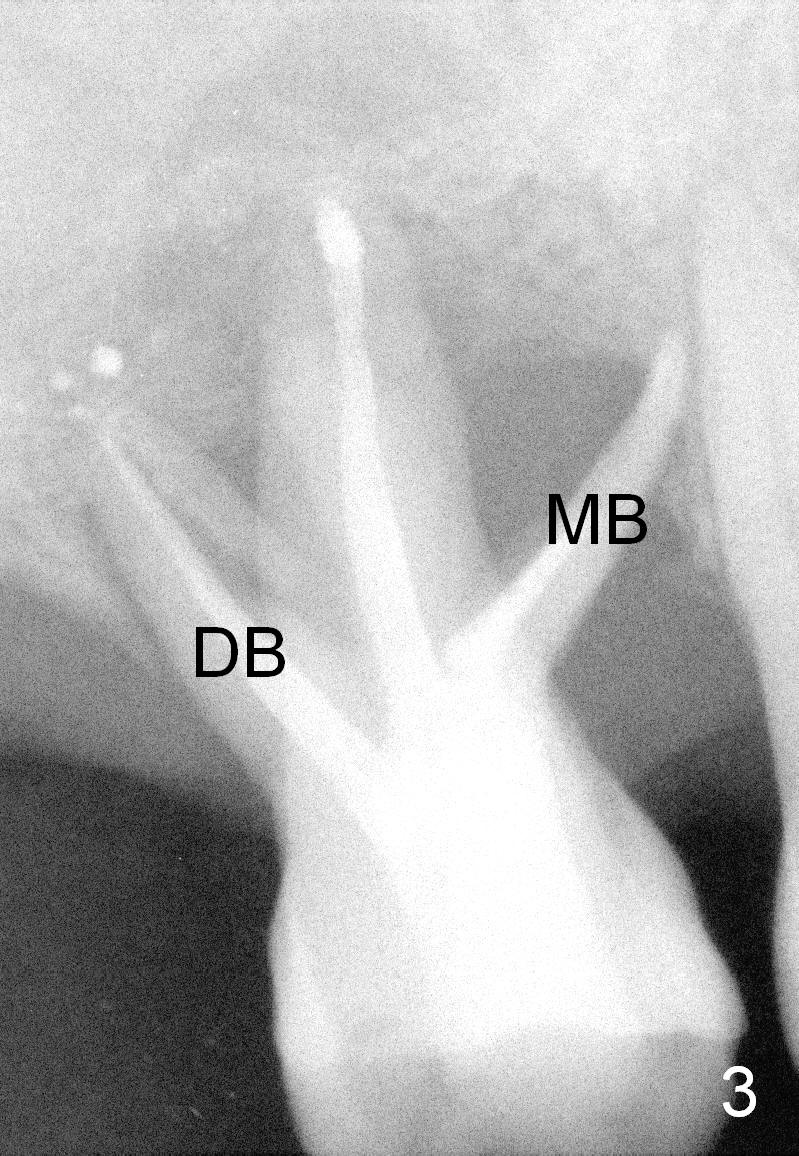

Two years post RCT, there is radiolucency around the MB root of the tooth #3 (Fig.1,2). Eleven days later, there is acute infection associated with MB and DB root fracture (Fig.3). According to the X-ray taken 11 days earlier (Fig.1,4), a long tissue-level implant (6x17 mm) is suitable for the site. In accordance with CBCT (coronal (Fig.5) and sagittal (Fig.6) sections) taken prior to RCT, a short bone-level implant (6.9x10 mm) is a more reasonable choice.